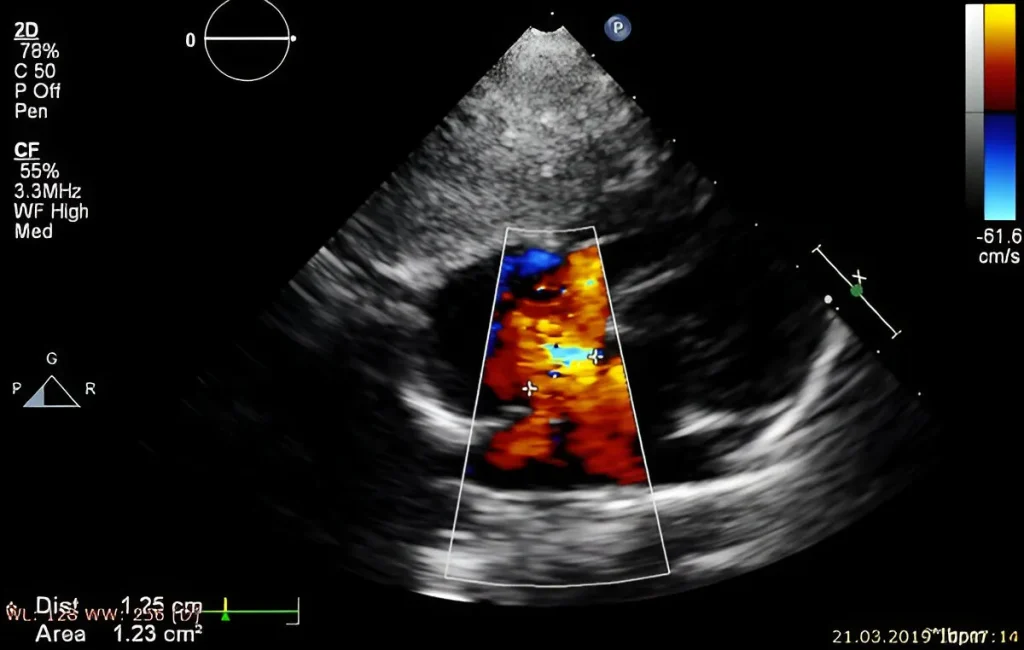

Benefits of Color Doppler for Placental Function and Umbilical Cord Blood Flow

Color Doppler ultrasound provides real-time assessment of placental function and umbilical cord blood flow. Therefore, it helps detect complications early to ensure optimal fetal health and timely pregnancy management. At Henotic Diagnostics, our experienced female radiologists offer a comfortable pregnancy scanning experience. Moreover, we follow ISUOG protocols and NABL-accredited standards for accuracy. Additionally, we specialize in 3D Uterine Artery Doppler, 3D Umbilical Artery Doppler, 3D MCA Doppler, and 3D Ductus Venosus Doppler in Kharghar & Navi Mumbai. Similarly, we provide Uterine Artery Doppler, Umbilical Artery Doppler, MCA Doppler, Placental Doppler, and 3D Power Doppler Angiography in Kharghar & Navi Mumbai for accurate results. As a result, you get trusted results for monitoring fetal oxygen flow and maternal blood supply assessment. Additionally, we offer affordable, expert Obstetrics (OBS) Doppler in Kharghar & Navi Mumbai. Book your Best Obstetrics (OBS) Doppler Near You or the Best Obstetrics (OBS) Doppler in Kharghar & Navi Mumbai today.